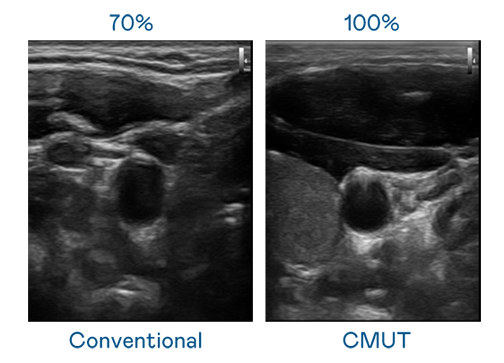

CMUT 技术是一种用电容式微机电元件来产生超音波讯号的技术。与传统 PZT 压电式技术相比,CMUT 频宽增加 30%,更宽频的超音波讯号让影像解析度大幅提升,是实现高影像品质医疗超音波扫描、促进精准医疗发展的关键技术。

超音波影像的解析度高低,首先取决于探头能发出的讯号频宽。BB贝博艾弗森 CMUT 可提供高清晰的超音波讯号,提供高频宽、高灵敏度、影像纹理细节更高的超音波影像,协助医护人员缩短影像判读时间及利用精准的医疗影像进行诊断。